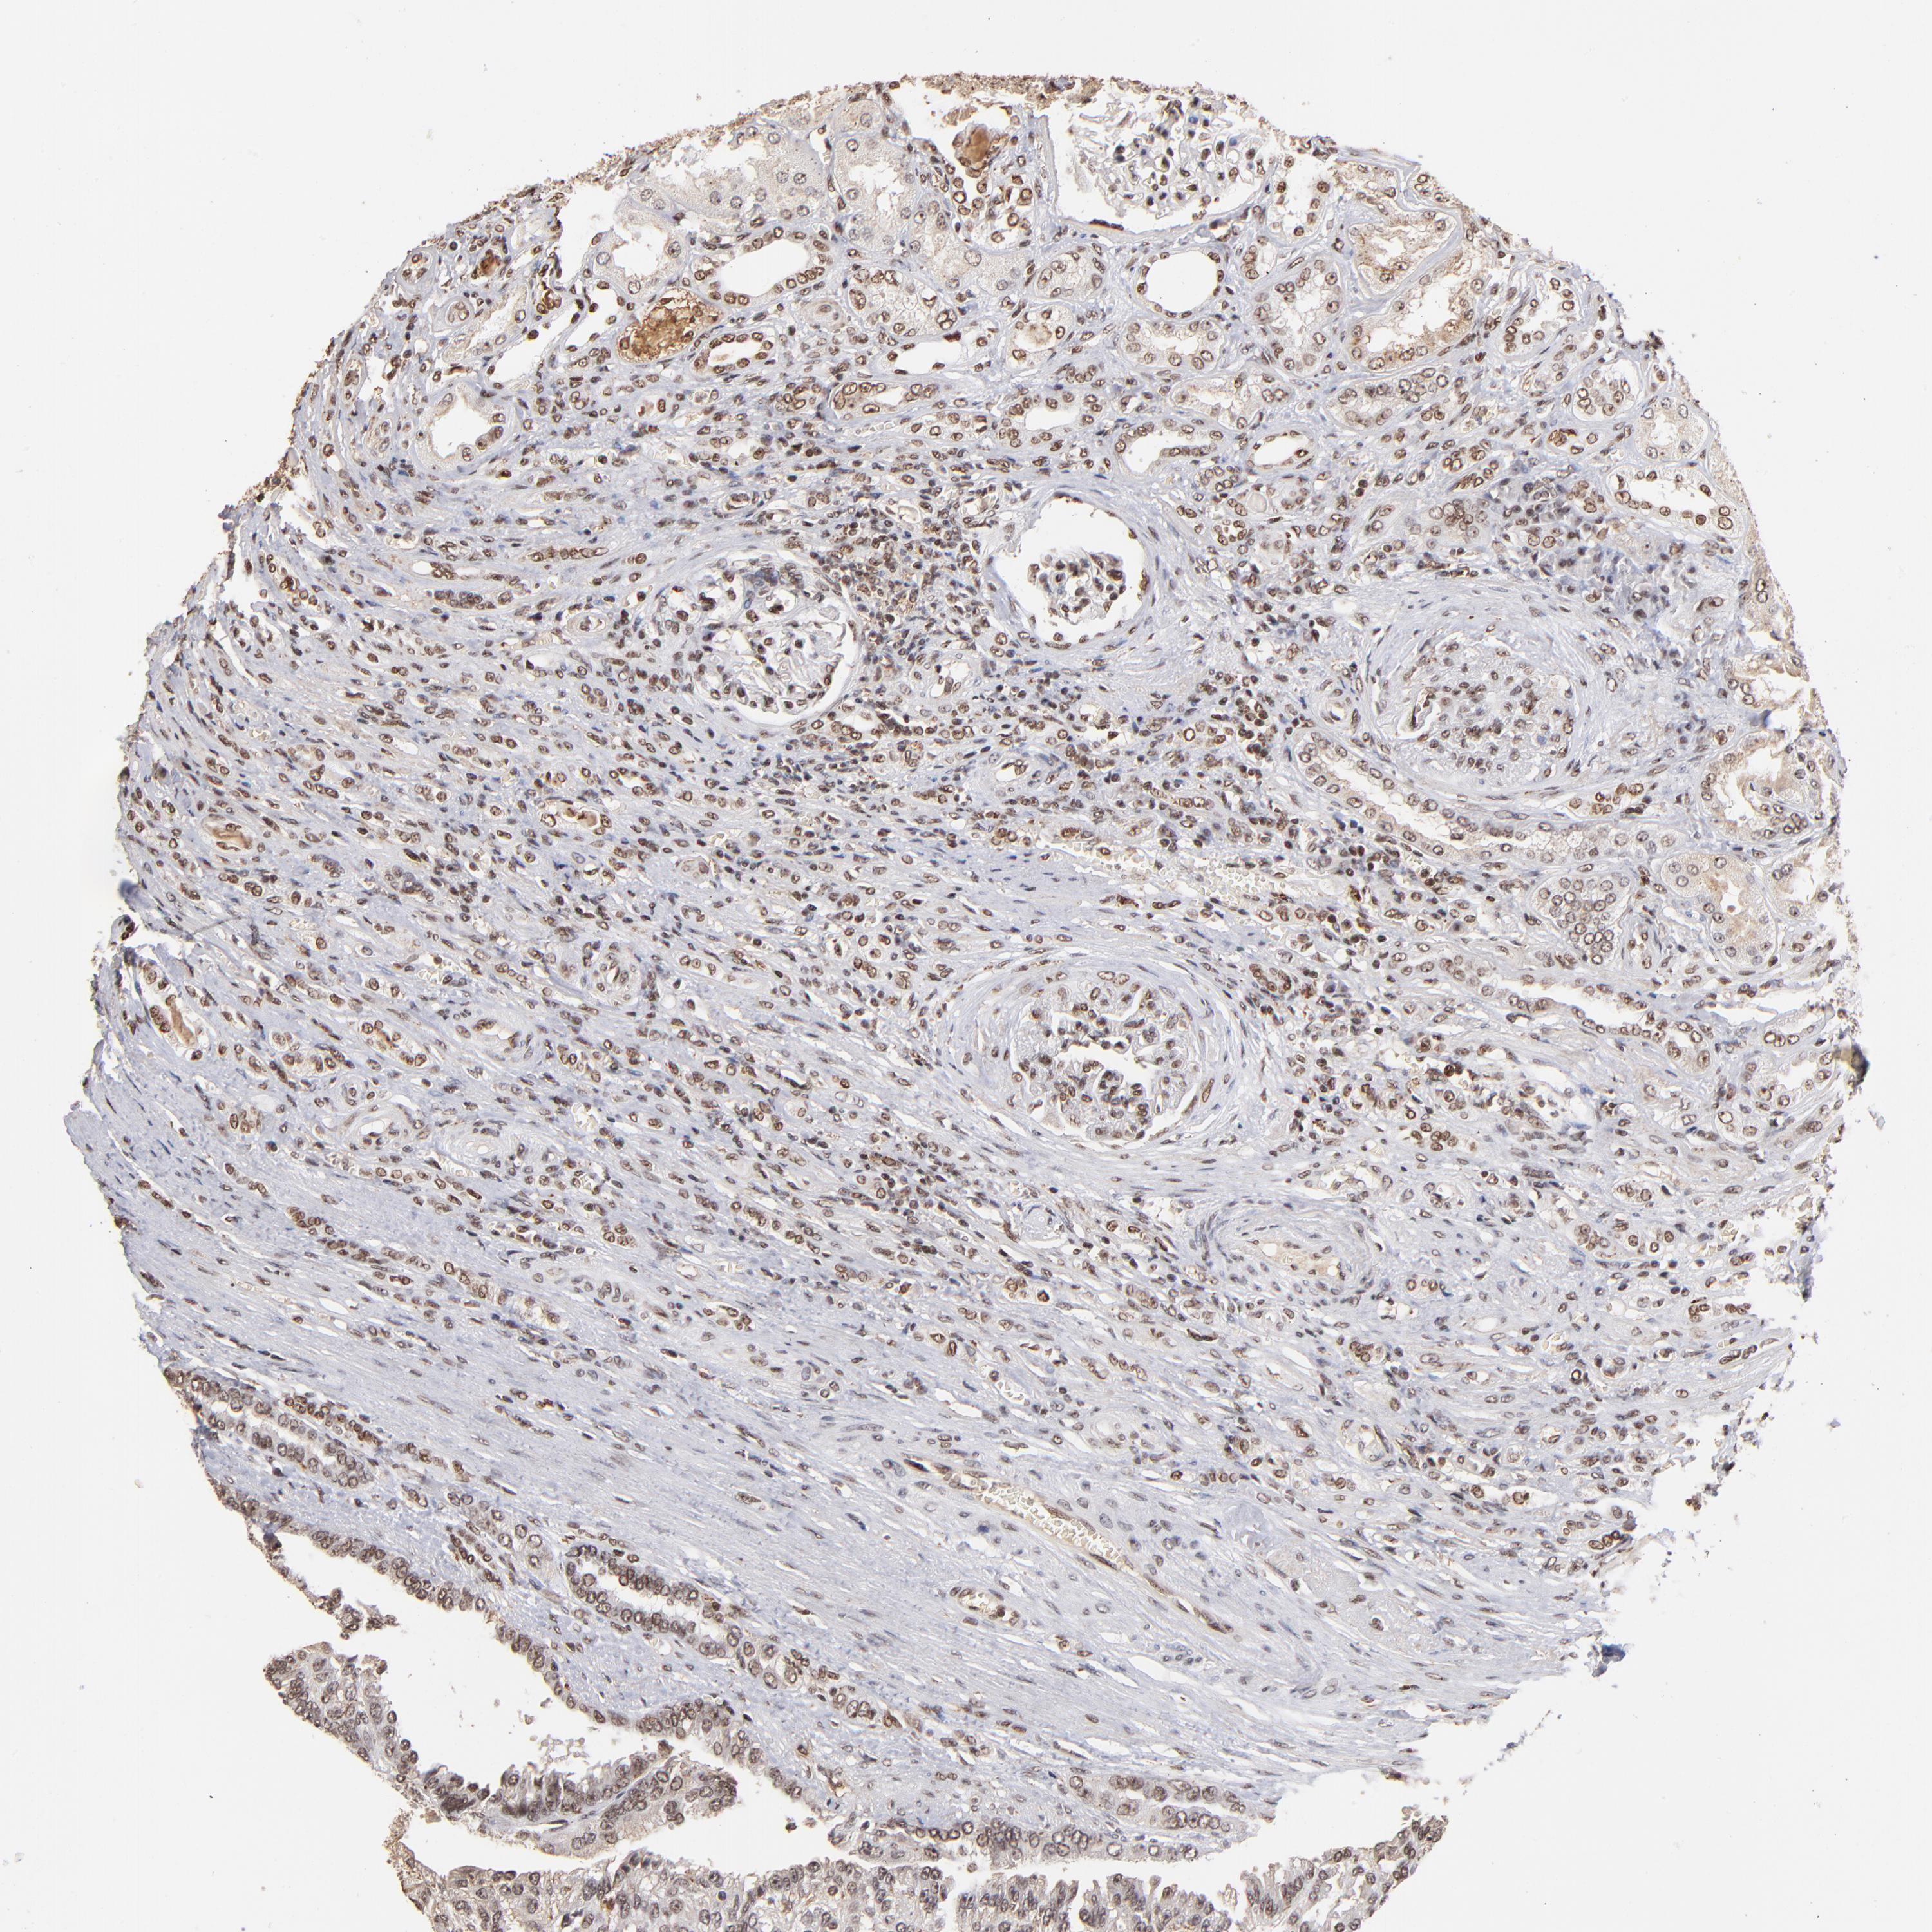

CANCER RENAL CANCER Show tissue menu

KICH TCGA KIRC TCGA KIRC VALIDATION KIRP TCGA PROTEIN RCC CPTAC PROTEIN EXPRESSION